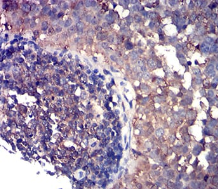

IHC    1/100 - 1/500